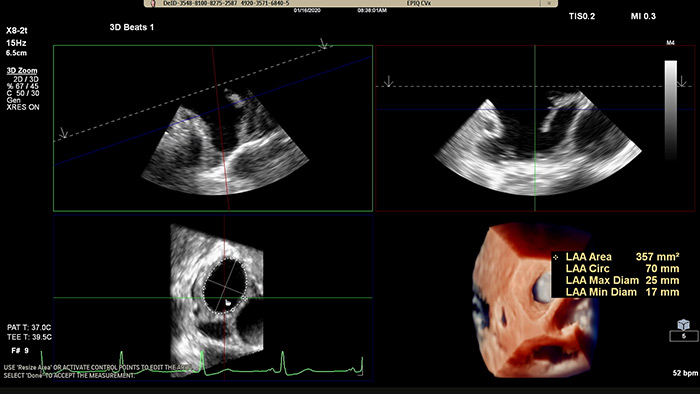

Assessing the left atrial appendage quickly, easily, intuitively.

The Philips LAA solution on EPIQ CVx.

Rapidly acquire LAA orifice measurements in both traditional rendering or in TrueVue Glass rendering, with 3D Auto LAA